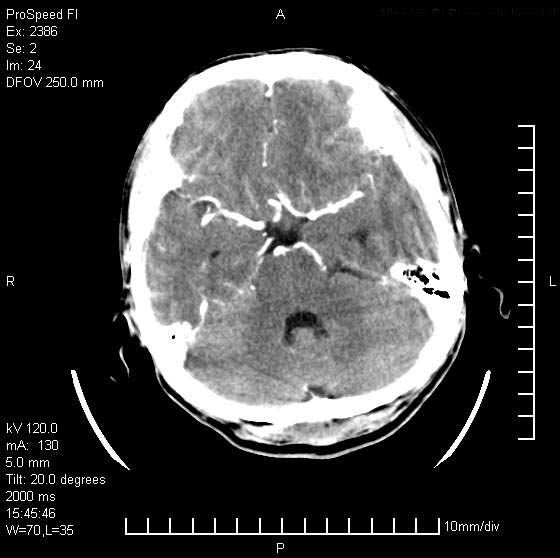

以下是引用天南地北在2007-9-19 18:43:00的发言:[br]典型慢性硬膜外血肿[br][br][本贴已被 天南地北 于 2007-9-19 18:44:11 修改过]

以下是引用曼一拍在2007-9-20 11:06:00的发言:[br]支持慢性硬膜下血肿.[br]慢性硬膜下积液:血肿有包膜,ct值稍高于脑脊液,增强可有染色。不典型者血肿可多呈梭形.是硬脑膜与蛛网膜之间的潜在腔隙内的血肿。[br]鉴别:[br]1\\硬膜外血肿:是颅脑外伤后脑膜或板障内血管破裂,血液在颅骨与硬膜之间积聚所致.通常是脑膜动脉破裂,也可因静脉窦破裂或颅骨的板障静脉出血,发生于外伤的着力部,常与颅骨骨折并存。脑膜动脉出血则急,若是板障静脉出血在则可有慢性。[br]2\\硬膜下积液:(硬膜下水瘤)[br]是由于蛛网膜破裂,脑脊液经蛛网膜破口进入硬膜下腔不能回流。或水肿阻塞而形成。[br]ct表现:颅骨内板下方新月形低密度区近似脑脊液密度;占位效应清,周围无脑水肿。[br]